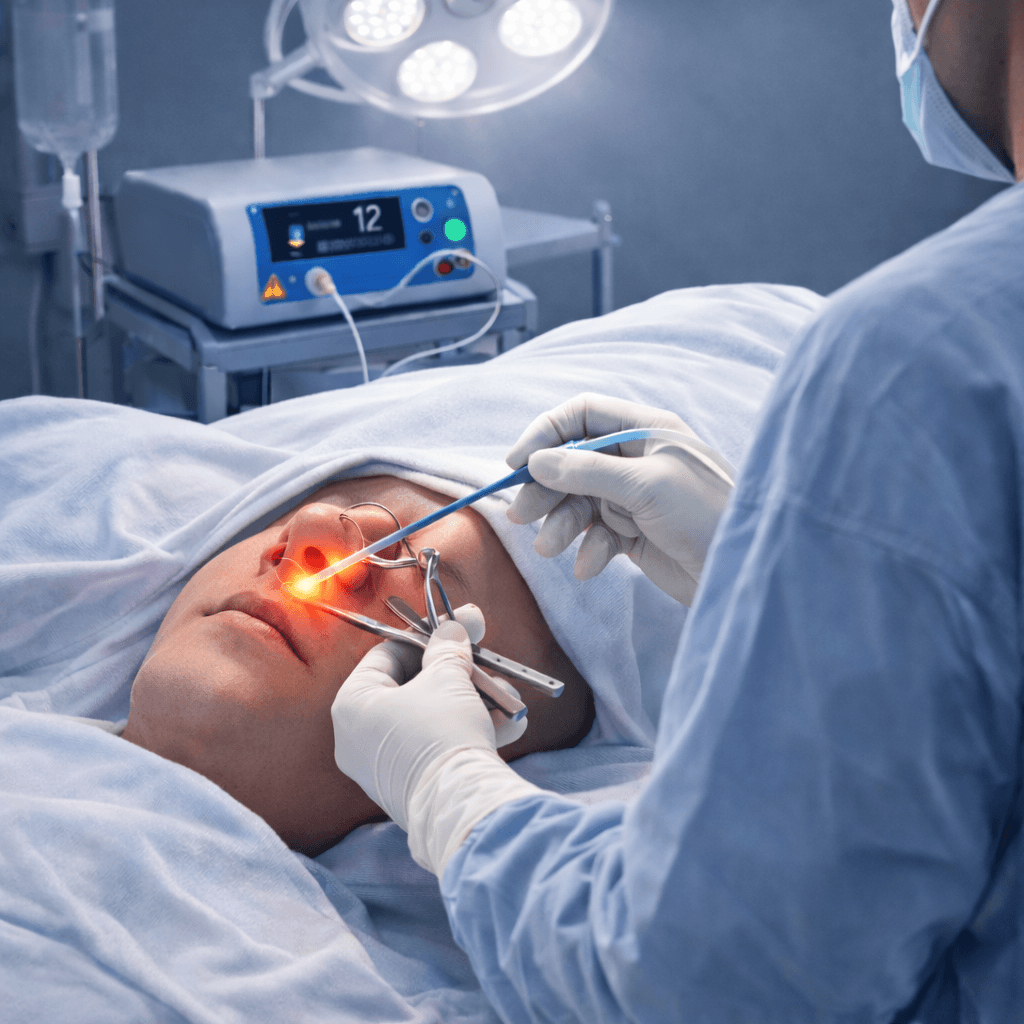

Robust Medical Diode Lasers, Fibres and Staplers

Our Product Applications

Minimally invasive procedures across multiple surgical specialities